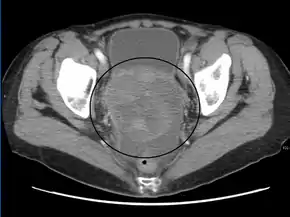

A very large ovarian cancer as seen on CT

Diagnosis of ovarian cancer starts with a physical examination (including a pelvic examination), a blood test (for CA-125 and sometimes other markers), and transvaginal ultrasound.[17][39] Sometimes a rectovaginal examination is used to help plan a surgery.[20] The diagnosis must be confirmed with surgery to inspect the abdominal cavity, take biopsies (tissue samples for microscopic analysis), and look for cancer cells in the abdominal fluid. This helps to determine if an ovarian mass is benign or malignant.[17]

CT scanning is preferred to assess the extent of the tumor in the abdominopelvic cavity, though magnetic resonance imaging can also be used.[19] CT scanning can also be useful for finding omental caking or differentiating fluid from solid tumor in the abdomen, especially in low malignant potential tumors. However, it may not detect smaller tumors. Sometimes, a chest x-ray is used to detect metastases in the chest or pleural effusion. Another test for metastatic disease, though it is infrequently used, is a barium enema, which can show if the rectosigmoid colon is involved in the disease. Positron emission tomography, bone scans, and paracentesis are of limited use; in fact, paracentesis can cause metastases to form at the needle insertion site and may not provide useful results.[20] However, paracentesis can be used in cases where there is no pelvic mass and ascites is still present.[20] A physician suspecting ovarian cancer may also perform mammography or an endometrial biopsy (in the case of abnormal bleeding) to assess the possibility of breast malignancies and endometrial malignancy, respectively. Vaginal ultrasonography is often the first-line imaging study performed when an adnexal mass is found. Several characteristics of an adnexal mass indicate ovarian malignancy; they usually are solid, irregular, multilocular, and/or large; and they typically have papillary features, central vessels, and/or irregular internal septations.[22] However, SCST has no definitive characteristics on radiographic study.[23]